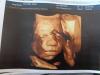

Во сколько недель лучше сделать 4д узи? Планирую идти в 26-28 недель,кто делал покажите фото ,заранее спасибо ☺️

Мы делали прям перед родами, фотки нет поблизости но малой родился один в один как на фото😁